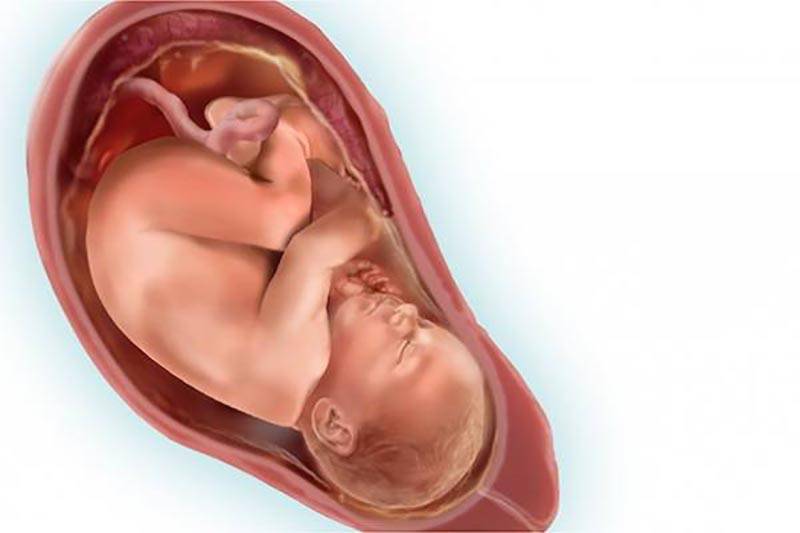

Плод 39 Недель Фото

Плод 39 Недель Фото 100 фото